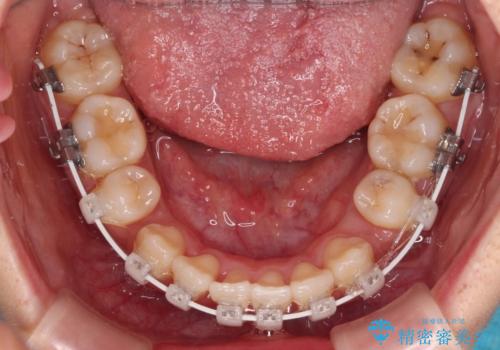

突出感の強い上顎前歯をしっかりと後方移動させるため、上顎の裏側の補助装置(リンガルアーチ)とアンカースクリューを併用しています。

上下左右の第一小臼歯を抜歯して、目立ちにくいワイヤー装置で矯正を行いました。

上下の保定用マウスピースの他に、デコボコの強かった下顎前歯にはワイヤーで保定をしています。